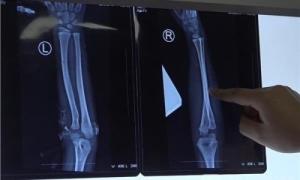

Bác sĩ cho biết về tình trạng của cậu bé: "Đứa bé bị gãy 2 tay, trên đầu có nhiều vết thương, có thể gây nguy hiểm đến tính mạng”. Họ cho biết thêm, mũi nạn nhân bị chém đứt, trên mặt có vết dao dài hơn chục cm, phía sau đầu có 3 vết chém. "Chúng tôi cho rằng, khi tự vệ theo bản năng, cậu bé đã cho 2 tay ra sau ôm lấy đầu, dẫn đến việc cả 2 tay đều bị thương nặng”, bác sĩ cho biết thêm.

Những vết thương nghiêm trọng có thể gây nguy hiểm đến tính mạng nạn nhân.